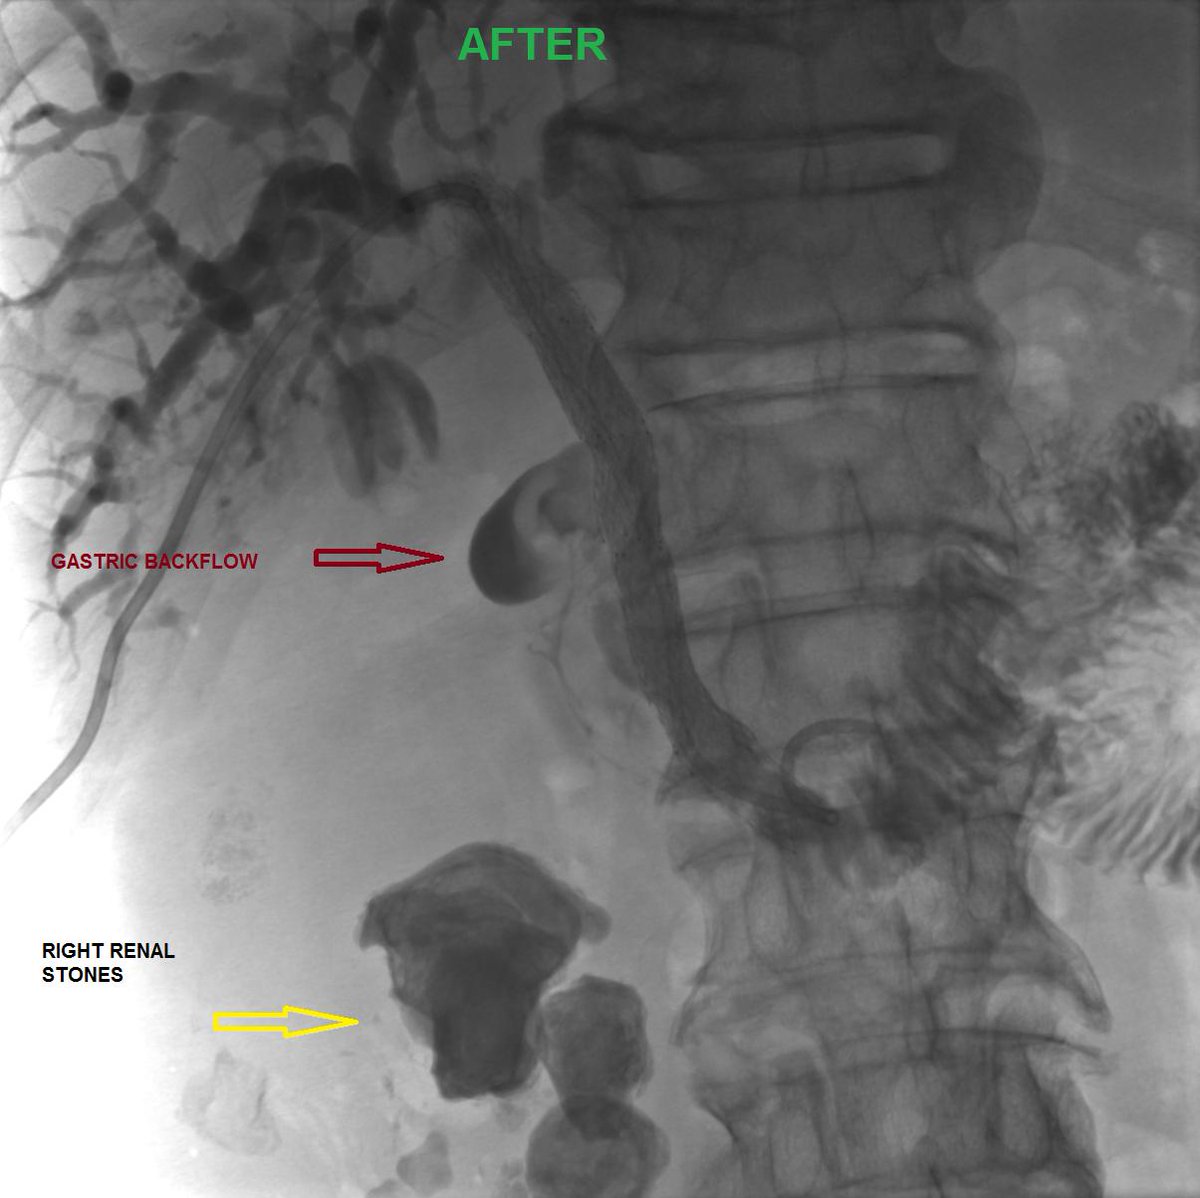

I'm obsessed with papillary lesions of the pancreatobiliary tract these days :D beautiful case of intraductal papillary neoplasm of cbd. No invasion.

#gipath#papillary#biliary pic.twitter.com/p2O4dNwp2J

Prikaži ovu nit -